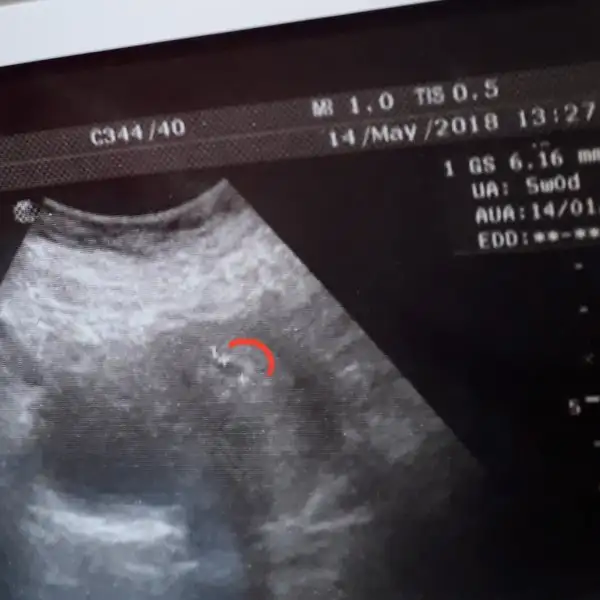

Cinsiyet nedir acaba 7+1 ama ultrasonda 6+4 çıktı

• 220B77C1-8537-4B43-A9C6-45BE8AE7FBD9.webp

15,6 KB · Görüntüleme: 278